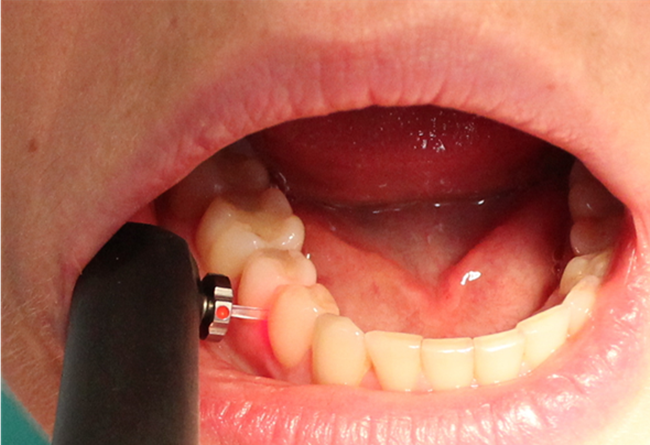

Należy pamiętać, że powierzchnia zęba powinna być przed badaniem diagnostycznym osuszona (w dalszej kolejności oczyszczona), a narzędziem zalecanym do badania dotykowego struktury tkanek zęba jest sonda WHO 621, małe upychadło kulkowe lub ekskawator (10). Do takiego badania należy zastosować również odpowiednie oświetlenie, pomocne może być powiększenie: lupy, kamera wewnątrzustna czy zastosowanie transiluminacji. Oceniając zmianę próchnicową, należy zwrócić uwagę na: lokalizację zmiany próchnicowej, obecność płytki nazębnej i przebarwień, stopień zaawansowania, ocenę aktywności, obecność (bądź brak) ubytku tkanek twardych. Najpowszechniej stosowanym systemem diagnostycznym w ocenie powierzchni stycznych jest badanie radiologiczne (11). Pitts i Rimmer w przeprowadzonych badaniach skorelowali przezierność zmian próchnicowych na zdjęciach radiologicznych z obecnością lub brakiem ubytku twardych tkanek. Żadna ze zmian wykazujących przezierność w połowie zewnętrznej grubości szkliwa nie wykazywała ubytku dostrzegalnego w badaniu klinicznym. Przezierność widoczna w połowie wewnętrznej grubości zębiny korelowała dodatnio z obecnością ubytku w 100% zbadanych zębów stałych i w 48% zębów mlecznych (12). Dodatkowymi często stosowanymi metodami, które mogą być wykorzystane w diagnostyce tego typu zmian, są metody oparte na zjawisku fluorescencji (DIAGNOdent pen, KaVo) (ryc. 3) i metody optyczne wykorzystujące wiązkę światła przechodzącą przez tkanki zęba (transiluminacja, FOTI, DIFOTI) (13).

Ryc. 3. Urządzenie DIAGNOdent pen z końcówką do oceny powierzchni stycznych.